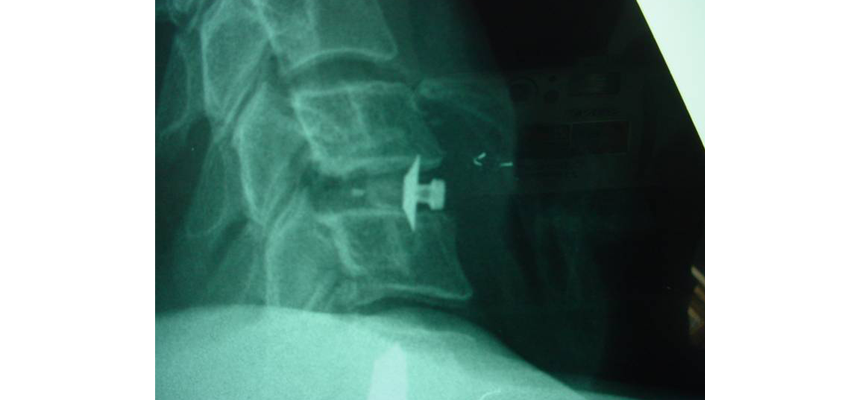

Locking cervical cage HRCC® is part of a range of stand alone cages offering a primary and secondary stability locking mechanism without the need of anterior plate fixation (please refer to instructional notice of HRCC® implants).

The cage is inserted according to routine technique, then the surgeon locks the cage by simple rotation of the instrument.

The blade penetrates into vertebral plates and prevents primary and/or secondary micro movements, advancing the fusion of the graft with vertebra.